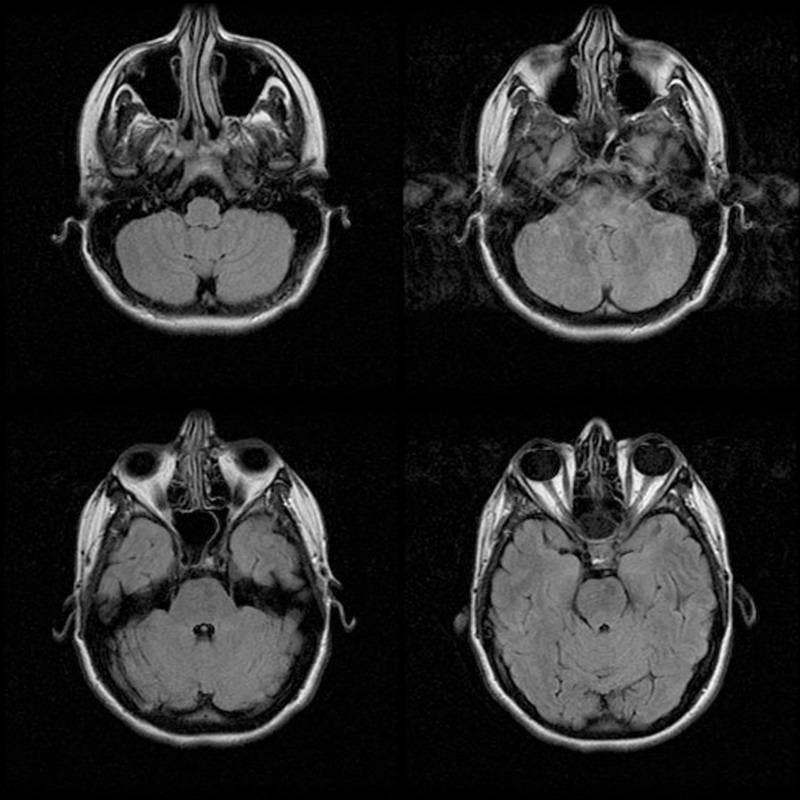

The emergency department is a challenging environment to practice medicine, primarily due to the pace and logistics of practicing emergency medicine. Cognitive errors and provider handoffs can lead to poor patient outcomes. By acknowledging and addressing cognitive errors, including premature closure, anchoring, and diagnosis momentum, we can potentially improve patient care. Additionally, by completing thorough, yet efficient sign-outs, as per The American College of Emergency Physicians' (ACEP) "Safer Sign Out Protocol," the chances of a poor outcome are further reduced. Below, a case of "migraine headache" is presented, highlighting cognitive errors and the risks associated with provider hand-offs in the emergency department.

急诊科是一个充满挑战的行医环境,主要是由于急诊医学的工作节奏和后勤保障。认知错误和医护人员交接班可能导致患者预后不良。通过认识并处理认知错误,包括过早下结论、锚定效应和诊断惯性,我们有可能改善患者护理。此外,按照美国急诊医师学会(ACEP)的“更安全的交接班协议”完成全面而高效的交班,可进一步降低不良后果的发生几率。以下展示了一个“偏头痛”病例,突出了急诊科的认知错误以及与医护人员交接班相关的风险。